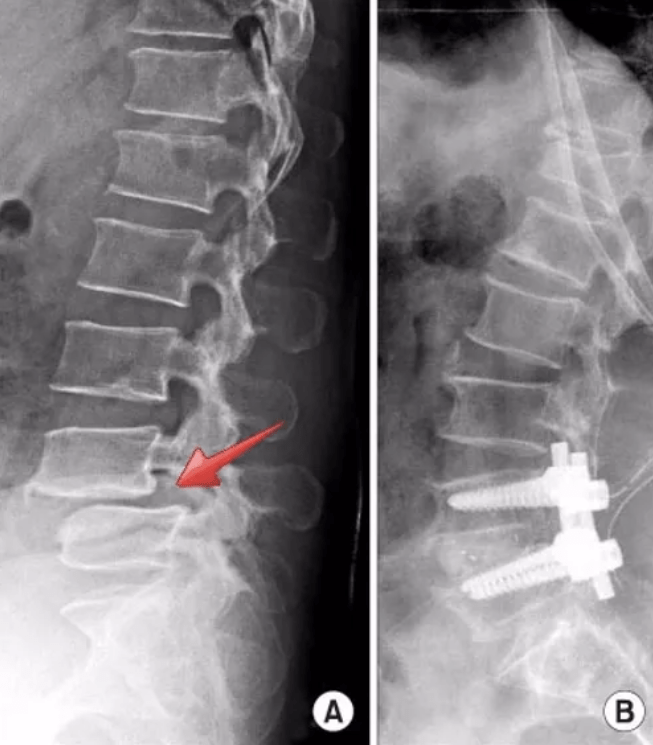

En temel anlatımıyla bel kayması (lomber spondilolistezis), 2 omurun birbiri üzerinden belli derecelerde kayarak omurilik ve ondan çıkan sinir köklerini sıkıştırması ve buna bağlı olarak hastada bulgular yaratmasıdır (Resim 1). Bu kayma bazen alt bel omurgası ile kuyruk kemiği (sakrum) arasındaki gelişimsel bir çatlağın ilerlemesi ile olur ve bir omur diğeri üzerinde kayarak erişkin tip bel kaymasını (istmik spondilolistezis) oluşturur. Bu tip bel kaymasından başka omurlar arası eklemlerin artritine ve omurlar arası disk yapısının bozulmasıyla oluşan dejeneratif tip bel kayması vardır.

Cerrahi dışı tedavi yöntemleri ile kontrol altına alınamayan ağrı, bacaklarda ve/veya ayakta kuvvet kaybı, idrar ve/veya gaita kaçırma bulguları olan hastalarda cerrahi tedavi düşünülmelidir. Bu durumda bası altındaki sinir kökünü rahatlatmak için dekompresyon denilen yani sinir köküne olan kemik basının ortadan kaldırılma işlemi yapılmalı, sonrasında da hastaya halkın platin vida koyma işlemi diye adlandırdığı, hekimlikte bizim füzyon işlemi dediğimiz omurgaların sabitleme işlemi yapılmalıdır (Resim 2). Masabaşı çalışanlarda hastalar 1 ay sonra işlerine dönebilirler. Ancak bedeni ile iş yapan hastalarda 2 ay gibi bir sürenin geçmesi gereklidir. Bazı hastalar ameliyat sonrası dönemde fiziksel tıp ve rehabilitasyon programına gereksinim duyabilmektedir.